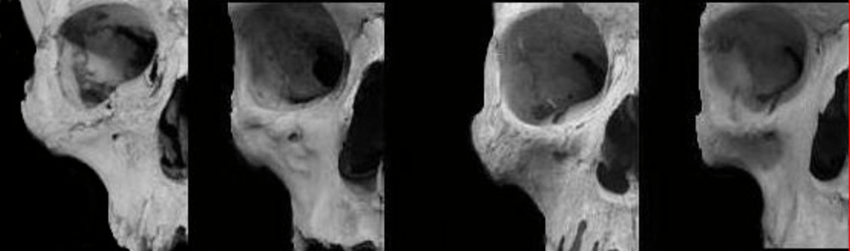

This is the canine fossa:

Phenotypes of the canine fossa at the left and right sides are different indicating

Here are a range of canine fossa, from shallow (left) to deep (right):

2355542 ariability of the canine fossa in current humans From left to right little expanded and